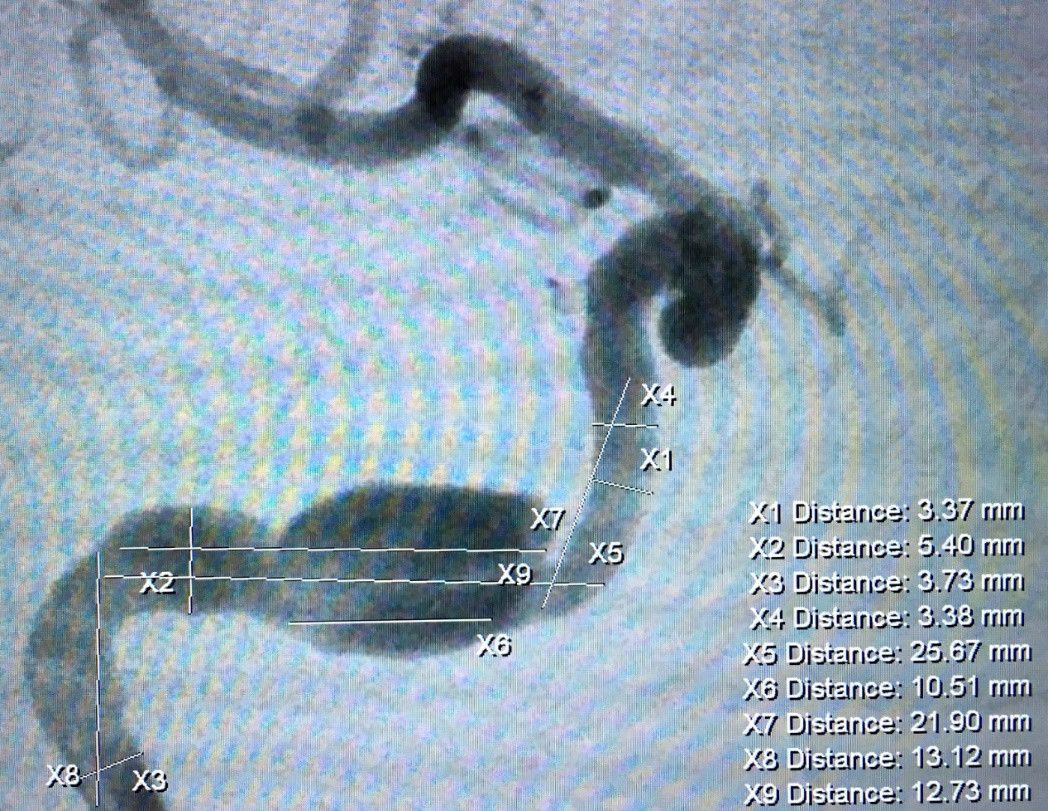

该患者因右眼外展受限引发复视,行DSA检查发现右侧颈内动脉岩骨段长节段夹层动脉瘤(图1)。夹层主体长径约18.3mm,其近端还有约5mm梭形扩张。传统的夹层动脉瘤治疗方法为支架辅助弹簧圈栓塞,需要多枚弹簧圈,同时多枚支架桥接覆盖夹层段对受累血管进行覆盖,且术后伴有较高的复发率。由于术中需要置入多根微导管,操作复杂;介入耗材使用多,花费高;局部占位效应明显,术后对外展神经压迫较持久,症状改善缓慢或是效果不满意;普通支架金属覆盖率低,术后复发率较高。结合病人动脉瘤的特点及临床表现,经过科室反复讨论,王东海教授治疗团队提出新思路并与家属沟通后,拟实施血管重建装置的血管内治疗。血管重建装置(Tubridge®)是由上海长海医院刘建民教授主导研发的有自主知识产权的国产支架,经过近6年的临床预试验后,被证实安全有效并于今年在国内上市。其特点是在血管内较高的金属覆盖率,良好的血管导向性,精准的尺寸适应不同条件的血管,低花费,低复发率使其在临床上具有广泛使用的空间。

图1:颅脑DSA检查提示右侧颈内动脉夹层动脉瘤,近端及远端夹层共累及血管长度约22mm。